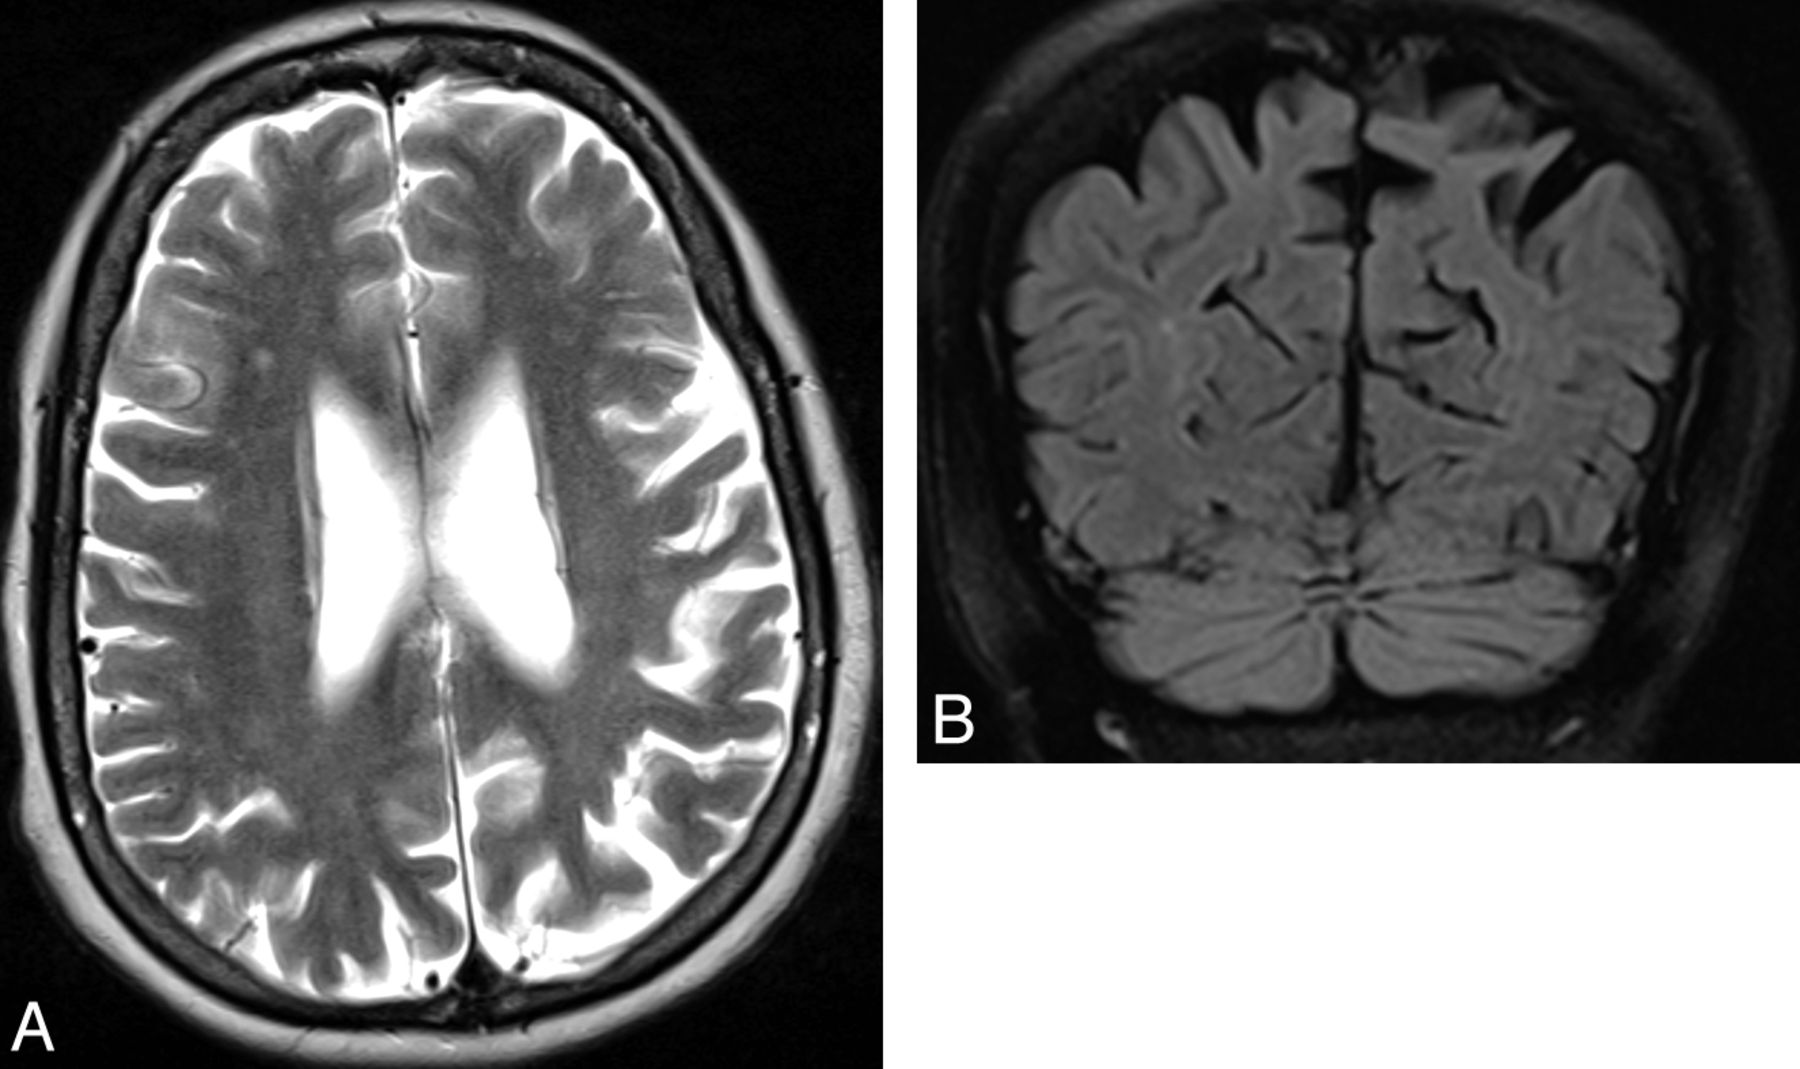

Structural MR imaging findings overlap in all MSA subtypes, independent of clinical presentation, though trends can be seen. In MSA-P, the putamen may demonstrate a rim of increased signal on T2-weighted sequences due to gliosis (Fig 1).5 In MSA with predominant cerebellar ataxia, pontocerebellar degeneration may result in visually apparent cerebellar and pontine atrophy, which, along with MSA-P to a lesser extent, is associated with increased signal on T2-weighted sequences in the middle cerebellar peduncles, cerebellum, and the pontine transverse fibers and raphe (“hot cross bun” sign) (Fig 2).

Axial T2-weighted MR imaging sequence in a patient with MSA with predominant cerebellar ataxia (A) demonstrating the “hot-cross bun” sign, which results from selective loss of myelinated pontine transverse fibers and raphe neurons. One study showed that the sign is 100% specific in differentiating patients with MSA from those with idiopathic Parkinson disease; however, it is only 50% sensitive.6 Marked pontine and cerebellar atrophy is also demonstrated. This olivopontocerebellar volume loss is shown on the sagittal T1-weighted sequences (B), where a middle cerebellar peduncle width <8 mm is demonstrated. All these signs are nonspecific in the wider population—for example, they can be seen in some spinocerebellar ataxia subtypes.

PSP accounts for a small minority of patients with parkinsonism. Neuropathologically, this tauopathy is characterized by neuronal degeneration of the nigrostriatal pathway, basal ganglia, and brain stem nuclei with deposition of neurofibrillary tangles. A number of MR imaging features suggestive of PSP have been described, such as dilation of the third ventricle and signal increase of the midbrain.5,26 Although often absent, atrophy of the red nucleus, frontal and temporal lobe, and an anteroposterior midbrain diameter of <17 mm can each differentiate PSP from MSA with at least 75% positive predictive value (Fig 4). If one uses a “MR parkinsonism index” [(pons/midbrain) · (middle cerebellar peduncle/superior cerebellar peduncle)], PSP can be prospectively distinguished from idiopathic Parkinson disease, MSA-P, and controls with 100% positive predictive value.27 Group studies additionally demonstrate that atrophy in the striatum and frontotemporal cortices, measured with volumetry and voxel-based morphometry, respectively, differentiate those with PSP from controls.9,28 Additionally, white matter atrophy in the subthalamic region can distinguish PSP from controls and idiopathic Parkinson disease when using voxel-based morphometry.29

Axial T2-weighted MR imaging sequence in a patient with PSP (A) demonstrating increased midbrain signal intensity (which is only 60% sensitive and 70% specific compared with MSA) and an atrophic midbrain with an anteroposterior diameter of <17 mm (which is 23% sensitive and 96% specific compared with MSA).5 The signs are nonspecific in the wider population—for example, midbrain signal intensity can be seen in Wilson disease and a severely atrophic midbrain can be seen in CBD. The concave posterolateral borders of the atrophic midbrain give it a “morning glory” flower appearance. The corresponding sagittal T1-weighted sequence (B) shows tectal atrophy with a “hummingbird” appearance.

CBD is a rare movement disorder presenting with rigidity, hypokinesia, and predominantly asymmetric cortical dysfunction. It is characterized by deposition of tau proteins in the form of neuronal inclusion bodies. On conventional MR imaging, asymmetric frontoparietal atrophy might distinguish patients with CBD from those with idiopathic Parkinson disease or MSA (Fig 7).26 To differentiate CBD from PSP, another tauopathy with frontal atrophy, measuring cortical atrophy with voxel-based morphometry or volumetry appears promising,41,42 as does probing motor thalamic involvement with ADC.43 With 18F-FDG there is asymmetric hypometabolism in the parietal lobe, while striatal dopamine-receptor binding is relatively preserved.44 Transcranial sonography shows substantia nigra hyperechogenicity but does not allow discrimination between idiopathic Parkinson disease and CBD or dementia with Lewy bodies.14

Axial T2-weighted MR imaging sequence in a patient with CBD (A) demonstrating asymmetric frontoparietal atrophy. The corresponding coronal FLAIR sequence (B) shows the asymmetric superior parietal lobules.